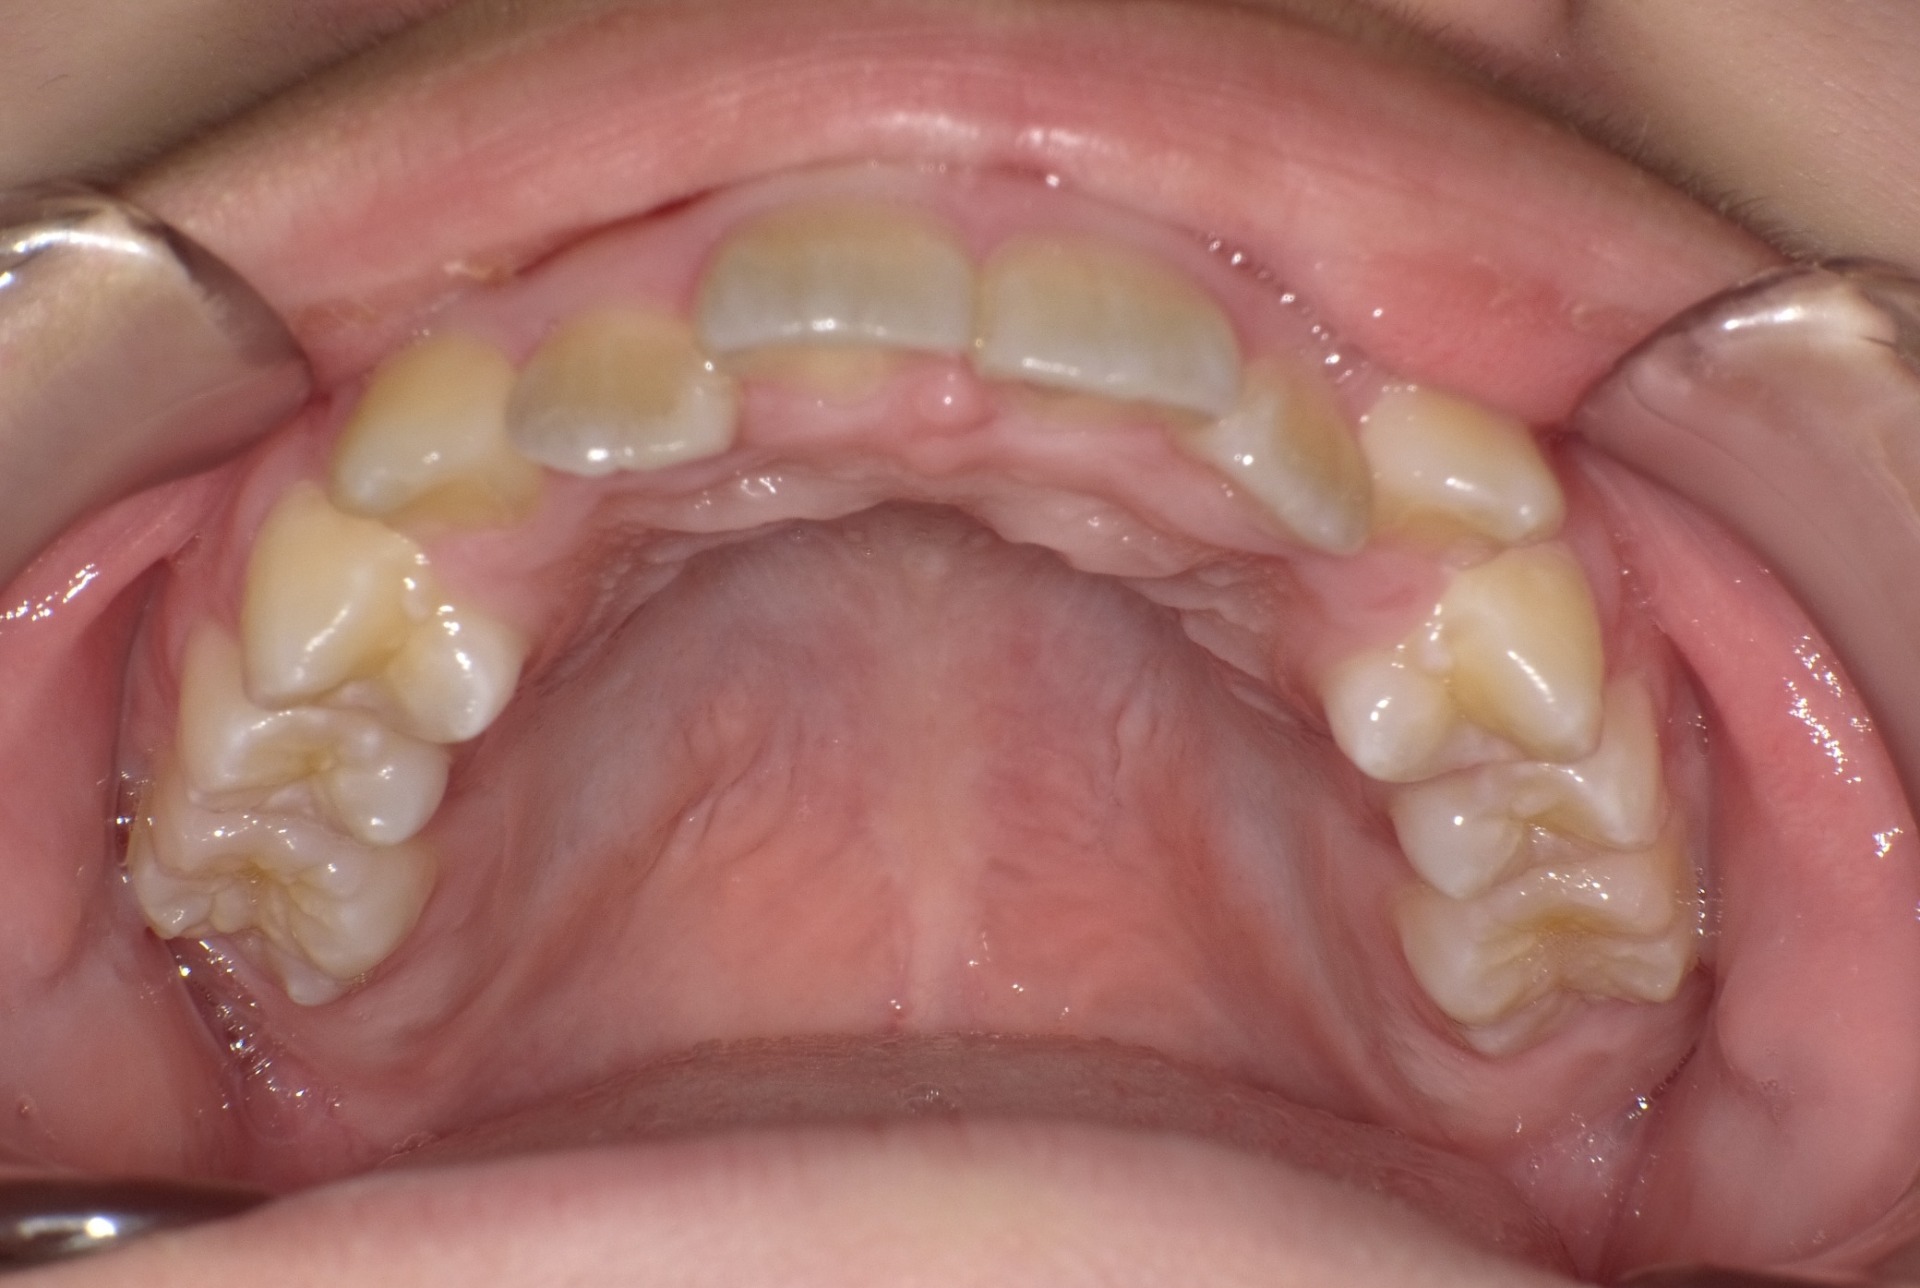

矯正前

| 症状 | 上顎前突 過蓋咬合 |

| 通院時の 年齢 |

8才1ヶ月〜15才10ヶ月 |